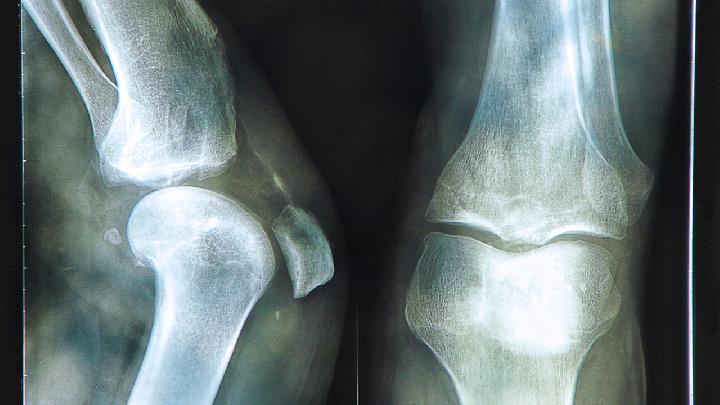

股骨头坏死

股骨头坏死形成的几种原因